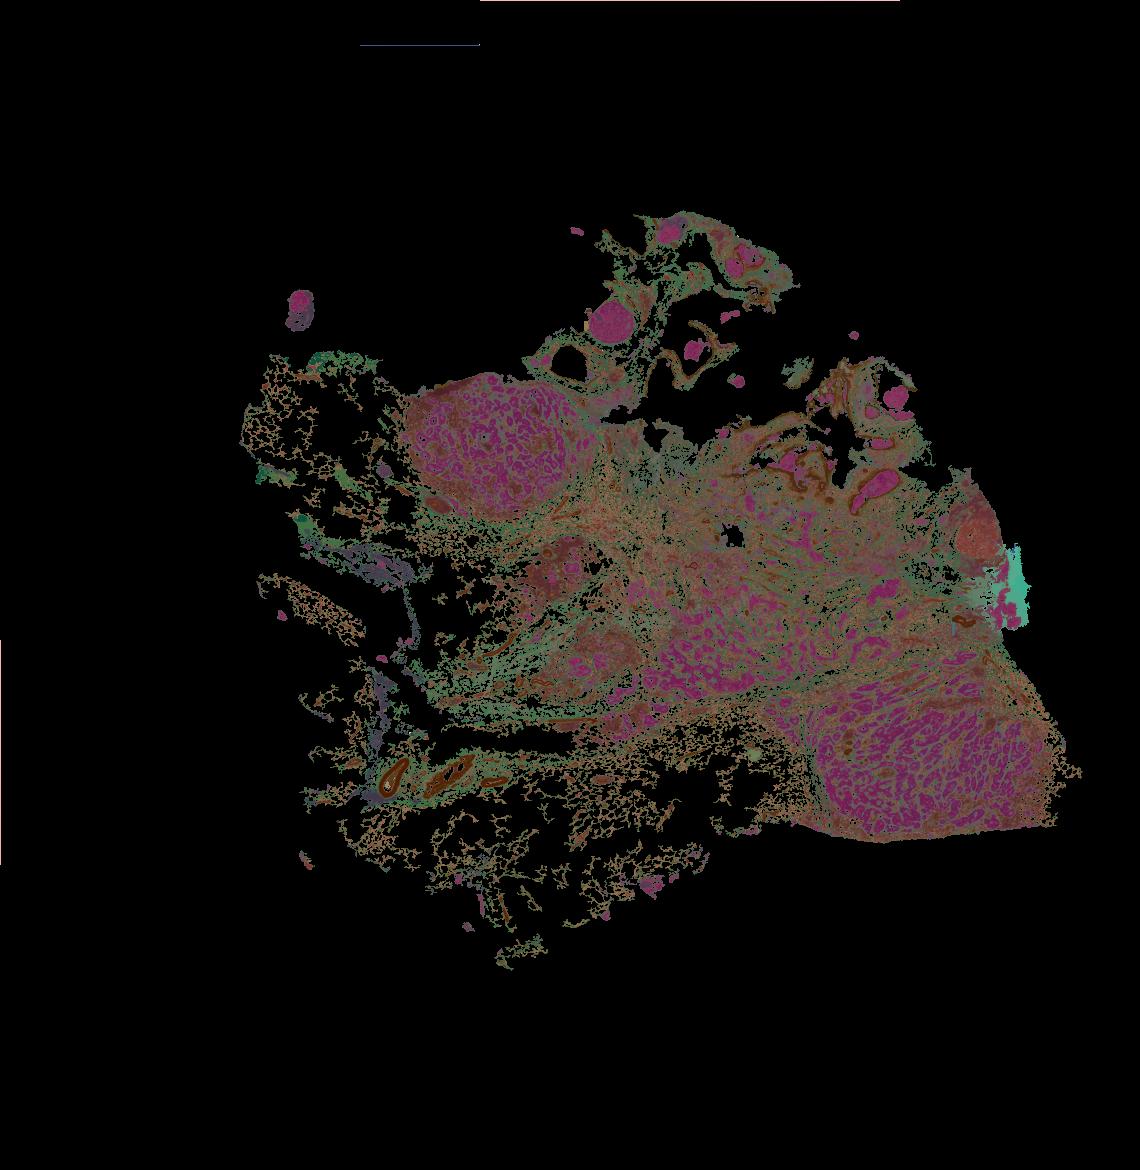

To study the spatial interactions among cancer and non-cancer cells1, we here examined a cohort of 131 tumour sections from 78 cases across 6 cancer types by Visium spatial transcriptomics (ST). This was combined with 48 matched single-nucleus RNA sequencing samples and 22 matched co-detection by indexing (CODEX) samples. To describe tumour structures and habitats, we defined ‘tumour microregions’ as spatially distinct cancer cell clusters separated by stromal components. They varied in size and density among cancer types, with the largest microregions observed in metastatic samples. We further grouped microregions with shared genetic alterations into ‘spatial subclones’. Thirty five tumour sections exhibited subclonal structures. Spatial subclones with distinct copy number variations and mutations displayed differential oncogenic activities. We identified increased metabolic activity at the centre and increased antigen presentation along the leading edges of microregions. We also observed variable T cell infiltrations within microregions and macrophages predominantly residing at tumour boundaries. We reconstructed 3D tumour structures by co-registering 48 serial ST sections from 16 samples, which provided insights into the spatial organization and heterogeneity of tumours. Additionally, using an unsupervised deep-learning algorithm and integrating ST and CODEX data, we identified both immune hot and cold neighbourhoods and enhanced immune exhaustion markers surrounding the 3D subclones. These findings contribute to the understanding of spatial tumour evolution through interactions with the local microenvironment in 2D and 3D space, providing valuable insights into tumour biology.